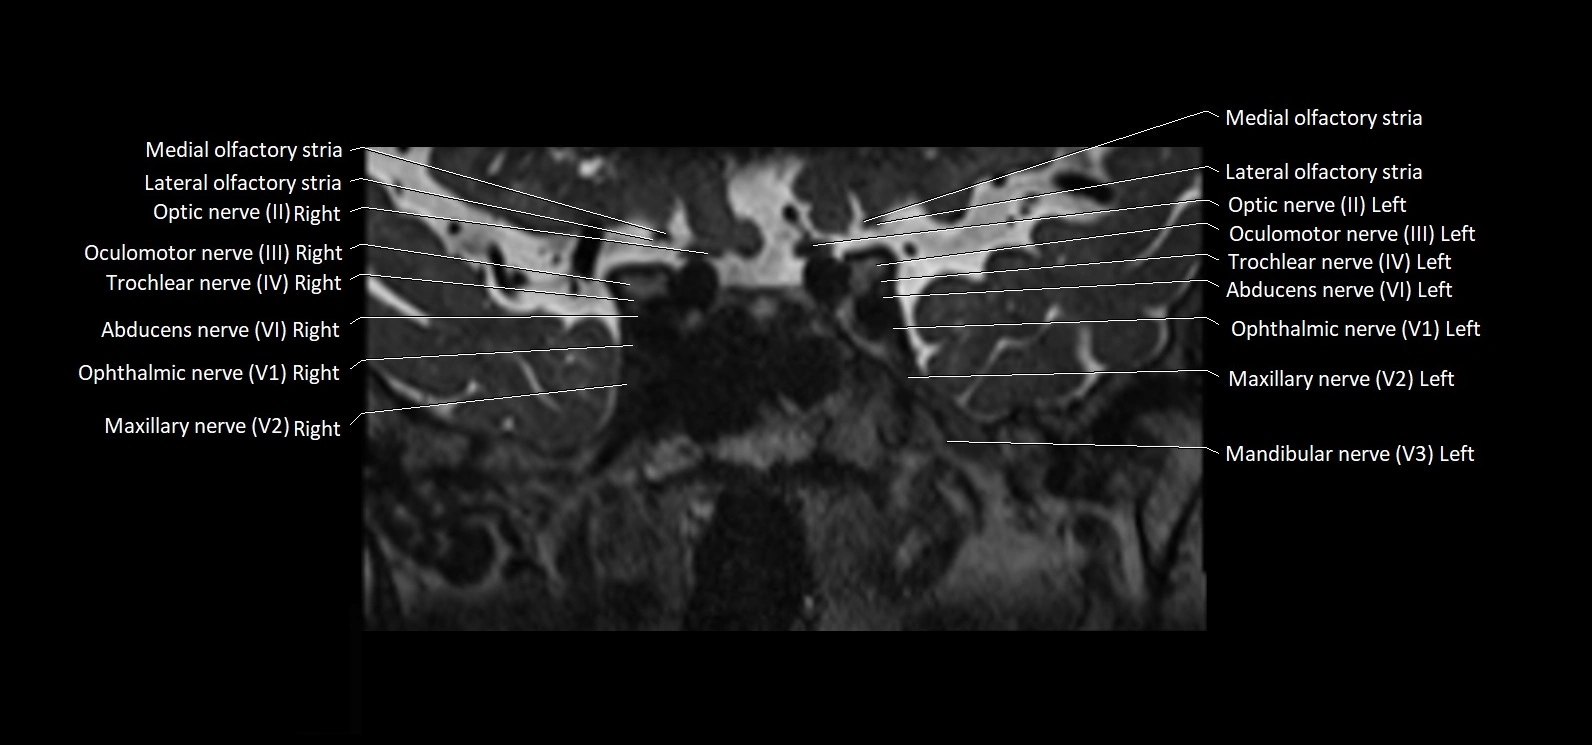

MRI Appearance

• The abducens nerve is a small, thin, linear structure

• Best visualized on high-resolution T2-weighted 3D MRI sequences (e.g., FIESTA or CISS)

• Seen as a hypointense (dark) line running from the brainstem at the pontomedullary junction, traversing the prepontine cistern, and entering Dorello’s canal under the petrosphenoidal ligament, then into the cavernous sinus, and finally the orbit

• May be challenging to visualize in standard MRI due to its small size

• Pathology may be inferred by absence, displacement, or enhancement of the nerve

MRI images

image